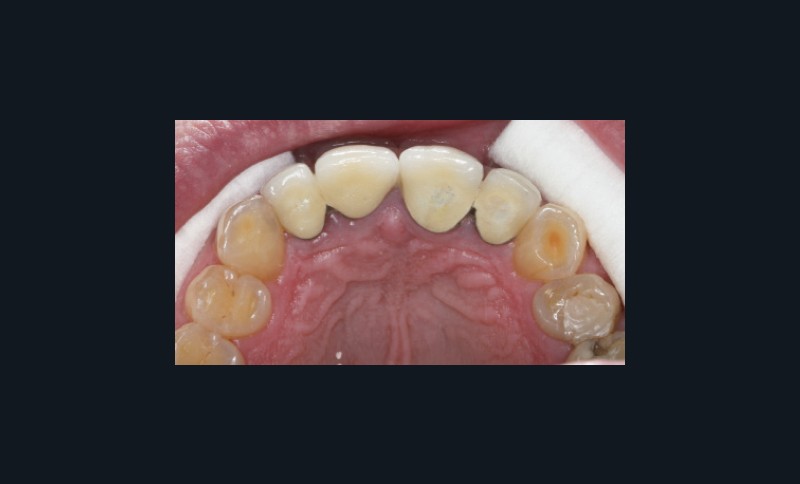

Dents : soins dentaires à réaliser sur 16, 26, 37.

Amputation mésiale de 46 ?, légères érosions.

Bruxisme : net avec attrition antérieure marquée en particulier en regard des coiffes céramiques.

Occlusion : décentrage gauche, création d’une légère béance antérieure probable conséquence

de l’atteinte de l’ATM gauche.